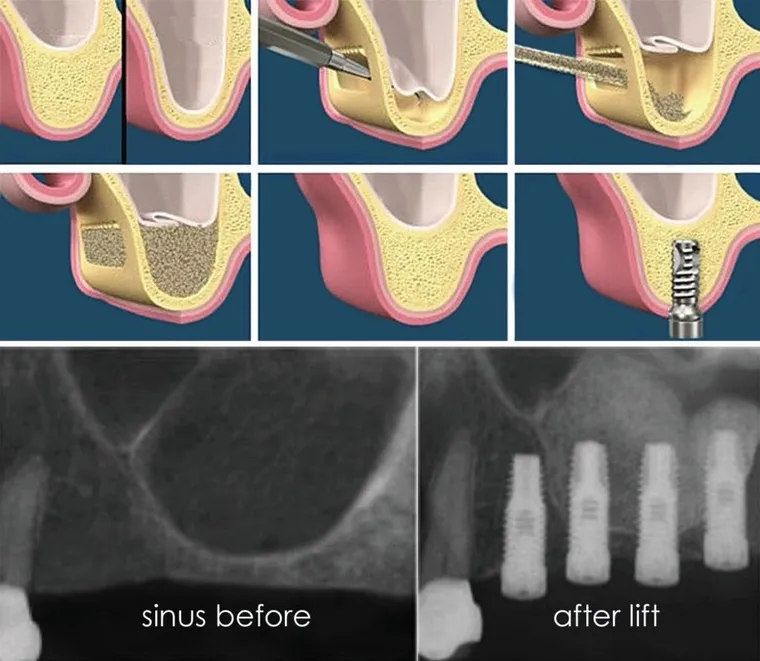

A sinus augmentation (or sinus lift) is a surgical procedure that adds bone to the upper jaw in the area of the molars and premolars to make it possible to place dental implants. It involves gently lifting the sinus membrane and placing bone graft material beneath it.

• Internal (Vertical) Sinus Lift – A less invasive method used when only a small bone boost is needed. The sinus is gently lifted through the implant site, and the implant is often placed at the same time.

• Lateral Window Sinus Lift – Used when more bone is needed. A small window is made on the side of the upper jaw to lift the sinus and add graft material. This approach allows for greater bone buildup.